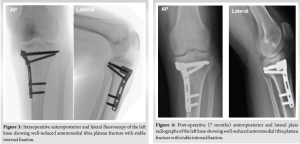

Prepping and draping were done in a sterile manner, and an anteromedial approach to the tibial plateau was used. Fracture exposed, and hematoma evacuated. There was an anteromedial plateau fracture, minimally displaced, and an anterior shell fracture not involving the articular surface. Under C-arm guidance, fracture reduction was done, and a 3.5 LCP L-shaped plate was placed on the anteromedial aspect. Three fully threaded cancellous screws were inserted proximally and 2 fully threaded locking screws were inserted in the shaft. Plate position was checked on anteroposterior and lateral C-arm views, which confirmed reduction and fixation. The anterior shell fracture was too small to be captured; thus, it was left intact (Fig. 3).

Postoperatively, the patient’s knee was immobilized in full extension using a hinged knee brace for the first 4 weeks to protect the fixation and facilitate early soft tissue healing. Passive range of motion (ROM) exercises was initiated at 4 weeks postoperatively, progressing to active-assisted and active ROM under supervised physiotherapy. Quadriceps strengthening and closed-chain exercises were gradually introduced between weeks 6 and 8. Partial weight bearing was permitted at 8 weeks, with progression to full weight bearing by 12 weeks, contingent upon radiographic evidence of healing. Throughout rehabilitation, emphasis was placed on joint stability, proprioceptive training, and return-to-function assessment tailored to the patient’s activity level. The patient was followed up in a 7-month period. In the last visit, the surgical scar was completely healed, the patient regained full knee ROM and was able to fully bear weight on it, and resumed his daily activities and job without complaining of pain. Patient was examined for ligamentous injuries which all were within normal range (Fig. 4 and 5).